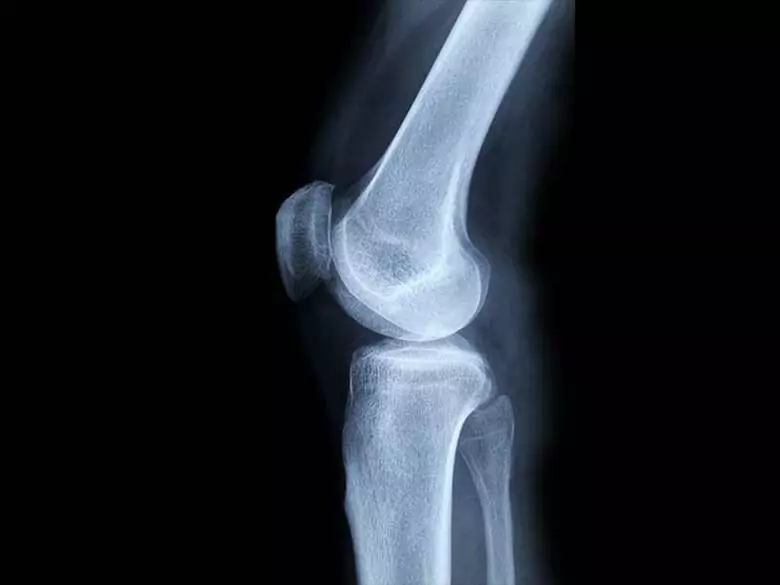

Although it is not the most common type of cancer, it is a very malignant disease that develops rapidly and gives metastases. Primary malignant bone tumours are difficult to diagnose. Due to its location and known causes, preventive measures cannot be indicated.